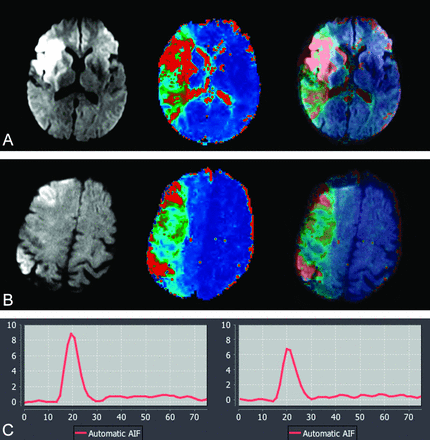

A, 62-year-old man with acute stroke; NIHSS score, 14. MR imaging was performed at 3T, 5 hours after the onset (from cohort group: 0.1 mmol/kg of gadolinium used for dynamic susceptibility contrast perfusion). B, 58-year-old man with acute stroke; NIHSS score, 16. MR imaging was performed at 3T, 3 hours after the onset (from study group: 0.05 mmol/kg gadolinium was used for dynamic susceptibility contrast perfusion). Serial DWI, Tmax, and superimposed DWI-Tmax demonstrate diagnostic image quality in both patients. A large perfusion-diffusion mismatch was identified with high confidence in both patients. The corresponding arterial input function curves are shown. There is approximately 24% lower arterial peak in half dose (6.7) compared with full dose (8.9). There is only small difference between the full width at half maximum of full dose (13) versus half dose (15).

DSC Perfusion

The mean ± SD of the volume of infarction on DWI and hypoperfusion with Tmax >6 seconds were 16.5 ± 7.6 (mL)/120 ± 48 (mL) for the full-dose group and 18 ± 9 (mL)/137 ± 70 (mL) for the half-dose group (P = .2). The mismatch ratios calculated automatically by the software demonstrated DWI-perfusion mismatch in all patients in both groups. DWI-perfusion mismatch was identified in 100% of the full-dose group and 90% of the half-dose group by both observers, with high confidence (r = 1).

There was no statistically significant difference in the SNR and background noise values between half- and full-dose groups (Table 3). When the baseline SNR of the initial phase of the perfusion study before arrival of contrast was evaluated, there was no significant difference (P = .6) between the mean baseline SNR of the full-dose (342 ± 101) and half-dose groups (330 ± 67), indicating an absence of significant recirculation effects. The maximum T2* signal drop values were higher in the full-dose group (P = .01). There was statistically significant higher AIF peak in the full-dose group (P = .002). There was however, no statistically significant difference between the FWHM of the AIF curves among the full-dose and half-dose groups (P = .1) (Table 3).